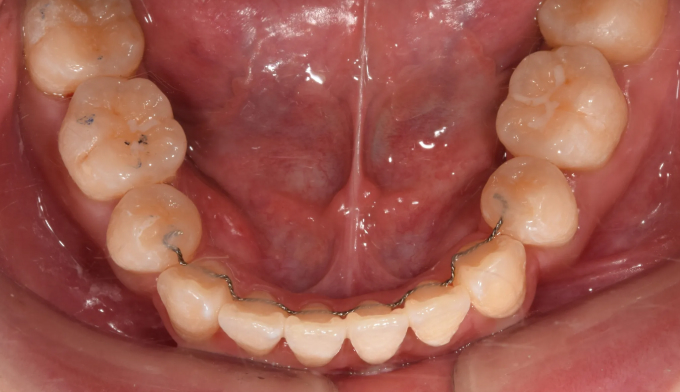

성인에서 기존의 앞니 치열이 매우 고르지 못하면, 교정 이후에 아래 앞니와 같은 블랙트라이앵글이 생길 수 있습니다. 마무리 교정 시 원한다면 해당 공간의 크기를 줄일 수 있습니다.

25개월의 교정기간동안 덧니,돌출입, 그리고 개방교합을 해소하였습니다.